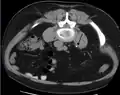

Otherwise a noncontrast helical CT scan with 5 millimeters (0.2 in) sections is the diagnostic method to use to detect kidney stones and confirm the diagnosis of kidney stone disease.[16][56][60][65][7] Near all stones are detectable on CT scans with the exception of those composed of certain drug residues in the urine,[58] such as from indinavir.

Where a CT scan is unavailable, an intravenous pyelogram may be performed to help confirm the diagnosis of urolithiasis. This involves intravenous injection of a contrast agent followed by a KUB film. Uroliths present in the kidneys, ureters, or bladder may be better defined by the use of this contrast agent. Stones can also be detected by a retrograde pyelogram, where a similar contrast agent is injected directly into the distal ostium of the ureter (where the ureter terminates as it enters the bladder).[60]